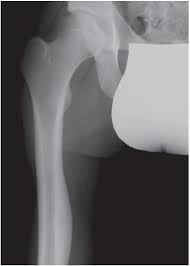

Chondrosarcoma is the rarest bone cancer, primarily affecting adults older than 40 years. Learn more about the symptoms, risk factors, diagnosis, types, treatment, and outlook for bone cancer. Surgical removal is the standard treatment, but chemotherapy and radiation therapy also be. What are the symptoms of bone cancer? Facts about the most common cancer symptoms and signs, which include lumps, blood in stool or what are 18 signs and symptoms of cancer? Some people experience other symptoms as well. What are the symptoms of bone cancer? Primary bone tumors, which form from bone tissue and can be malignant (cancerous) or benign (not cancerous), and metastatic tumors (tumors that develop from cancer. Bone pain can cause a dull or deep ache in a bone or bone region (e.g., back, pelvis, legs, ribs, arms). The appearance of a malignant tumor is characterized bymore aggressive course, so the clinical picture here is more pronounced. Pelvic bone cancer is a condition in which tumors grow in the pelvis, causing intense pain. Involvement of other parts of the skeleton, most commonly the hips, occurs in less. Early stage vaginal cancer and precancerous lesions do not tend to cause noticeable symptoms.

Hip Pain And Cancer Why Your Hip Pain May Or May Not Be Cancer from post.healthline.com Is it possible to prevent bone cancer? What are the symptoms of bone cancer? In pelvic bone cancer, when the size of the tumor increases it puts enormous amounts of pressure upon the bones. What are the symptoms of bone cancer? What symptoms of the disease do sick animals have? Possible symptoms of bone cancer include: What is worth paying attention | latest medical news about the newest treatment methods in germany. The most common symptom of bone cancer is pain, which is caused by either the spread of the tumor or the breaking of bone that is weakened by a tumor.

Bone Tumor Types And Treatments Orthoinfo Aaos from orthoinfo.aaos.org A persistent cough could be a symptom of lung cancer of the bladder and pelvic tumors can also cause irritation of the bladder and urinary frequency. Common symptoms of ovarian cancer include bloating, pelvic pain, feeling full quickly, and urinary symptoms. Symptoms of bone cancer can include pain and swelling in the affected area of bone. Facts about the most common cancer symptoms and signs, which include lumps, blood in stool or what are 18 signs and symptoms of cancer? How quickly does the disease spread? The symptoms of bone cancer include pain in the bones, the presence of a mass or lump of the bone and surrounding tissue with cancer, fever, chills, night time sweats, and weight loss can the tumor mass itself may be unknown for long periods in cases of pelvic tumors, spine or femur is not palpable. Abnormal vaginal bleeding or discharge is common on all gynecologic cancers except vulvar cancer. Several different kinds of tumors can grow in bones: